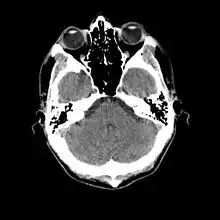

- معلوم شد که سیتی اسکن مغزی (که در سال ۱۹۷۲ ابداع شده بود) یک وسیلهٔ تشخیصی عالی برای یافتن تومورهای مغزی کودکان است، از جمله آنهایی که در بیماری توبروز اسکلروزیس دیده میشود.[45]

- برشنگاری با گسیل پوزیترون (که در سال ۱۹۸۱ اختراع شده بود) با نوار مغزی و سیتی اسکن مقایسه شد و مشخص گردید که قادر است تا محل تکمههای تصلبی صرعزا را در قشر مغز هویدا سازد که قابل تشخیص با روشهای دیگر نبود.[49]

- امآرآی (که در سال ۱۹۸۰ اختراع شده بود) برای نخستین بار در تشخیص نواحی مغزی مبتلا به توبروز اسکلروزیس در یک دختر مبتلا به این بیماری استفاده شد.[51]

- معلوم شد که امآرآی حساسیت و اختصاصیت بیشتری نسبت به سیتیاسکن دارد. در یک مطالعه بر روی ۱۵ بیمار، امآرآی توانست در ۱۲ بیمار، ندولهای تحتاپاندیمی را که به درون بطنهای جانبی رشد کرده بود، تغییر ساختاری قشر مخ در ۱۰ بیمار (که با تکمههای تصلبی مطابقت داشت) و گشادشدگی بطنهای مغزی را در ۵ بیمار تشخیص دهد و یک تومور آستروسیتوم اثباتشدهٔ قبلی را از ندولهای تحتاپاندیمی در یک بیمار تمیز دهد.[52]

- ۱۹۸۷

- مشخص شد که امآرآی قادر است شدت بیماری را پیشبینی کند (صرع و تأخیر تکاملی). در یک پژوهش بر روی ۲۵ بیمار، ثابت شد که رابطهای میان تعداد تکمههای قشر مغز و شدت بیماری وجود دارد. در مقابل، سیتیاسکن پیشبینیکنندهٔ مفیدی نیست، اما نسبت به امآرآی در تشخیص ندولهای کلسیفیه برتری دارد.[53]

- در مطالعهای بر روی ۶ کودک مبتلا به این بیماری، مشخص شد تکمههای قشری که در امآرآی یافت میشود، دقیقاً همان کانونهای پُربسامد نوار مغزی هستند. بهویژه تکمههای لوب پیشانی، با بروز تشنجهای سخت و دیردرمان مرتبط هستند.[55]

- ثابت شد که برای تشخیص تکمههای کوچک تصلبی مغز، بهویژه آنهایی که تحت قشری هستند، روش تصویربرداری فِـلِـیر[persian-alpha 6] در امآرآی، به مراتب بهتر از روش استاندارد تی ۲[persian-alpha 7] است.[61][62]